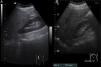

Las características ecográficas, difíciles de observar, son reflejo de los cambios histológicos, pudiendo aparecer: alteración difusa de la ecogenicidad, con brillo acentuado en las triadas portales, diferente grado de hepatomegalia homogénea y engrosamiento de la pared vesicular con contenido de barro biliar (colecistitis aguda alitiásica) (fig. 3B).

Esteatosis leve. Aumento difuso mínimo de la ecogenicidad hepática (fig. 3A).

Redistribución del volumen. En fases iniciales el hígado puede aumentar de tamaño, pero su tendencia es hacia un hígado de tamaño reducido (atrófico) con un aumento relativo del lóbulo izquierdo y/o del lóbulo caudado (presentando un tamaño >35mm en el eje anteroposterior y una relación LC/LHD>0,65) (fig. 4D)26,27.

Figura 4.Signos de hepatopatía crónica. A)Corte oblicuo de hipocondrio derecho. Dilatación de la porta y ascitis. B)Corte longitudinal de hipocondrio izquierdo. Esplenomegalia y ascitis. C)Corte longitudinal de epigastrio. Bordes irregulares del lóbulo hepático izquierdo. D)Corte transversal de hipocondrio derecho. Hipertrofia del lóbulo caudado.

Superficie nodular. Visualizada como irregularidad del contorno hepático, evidenciándose mejor ante la presencia de ascitis y causada por nódulos regenerativos y fibrosis (fig. 4C).

Alteraciones de la vena porta y del eje esplenoportal28-30. Medición de la vena porta a nivel del hilio hepático superior a 13mm, nula o pobre modificación de su volumen con los cambios de presión abdominal secundarios a la dinámica respiratoria (aumento inferior al 20% de su volumen durante la inspiración)31 y disminución de la velocidad32 e inversión del flujo venoso (hepatófugo) (fig. 4A)33.

Esplenomegalia. Volumen aumentado (diámetro bipolar >13cm o la superficie del eje en el corte longitudinal del órgano >60cc), siempre relativo al peso del paciente. Y medición de la vena esplénica, a nivel del hilio, mayor de 9mm (fig. 4B).

Ascitis. Presencia de líquido libre (sonoluscente) en la cavidad peritoneal rodeando a órganos y asas intestinales, en mayor o menor medida en función del volumen (figs. 4A y B).